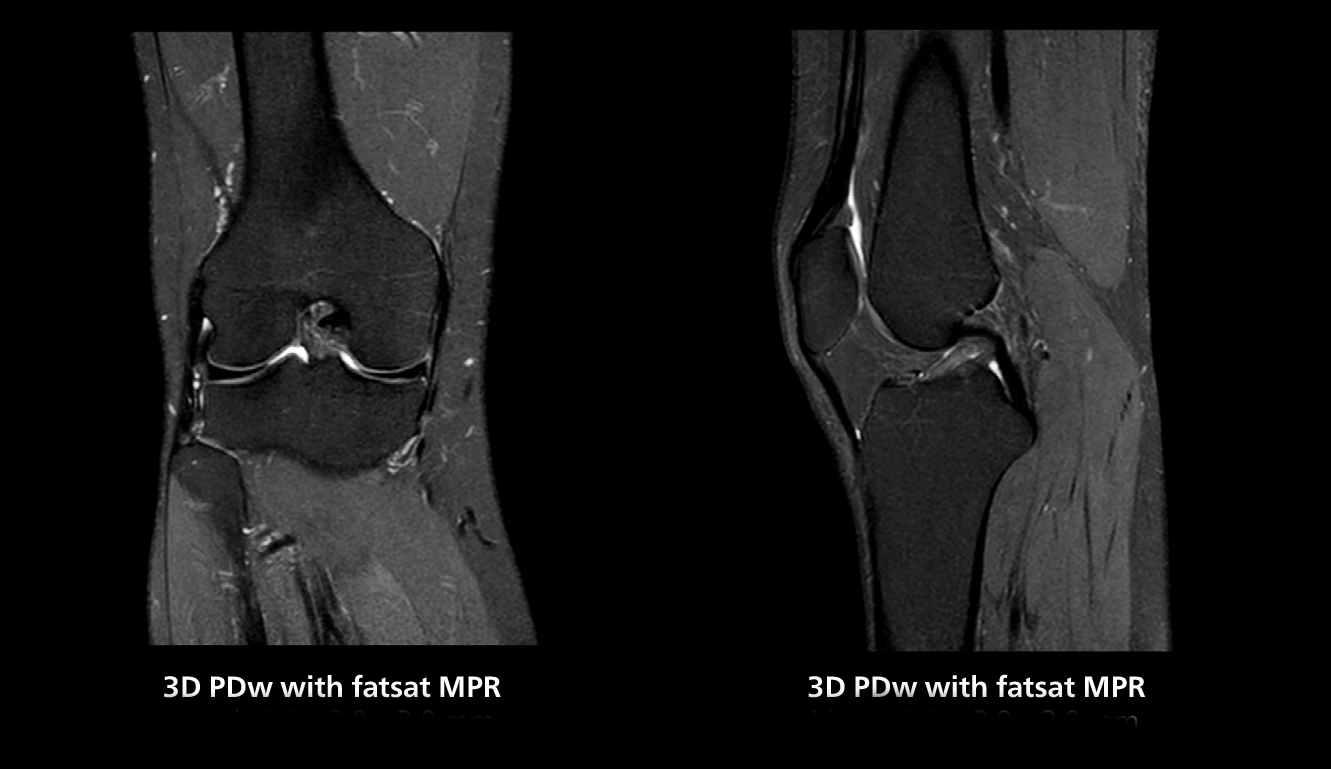

3D knee imaging

The isotropic high resolution 3D sequence in this MRI case allows for reformatting to obtain other orientations with high quality. Acquired on the MR 5300 system.

3D knee imaging

The isotropic high resolution 3D sequence in this MRI case allows for reformatting to obtain other orientations with high quality. Acquired on the MR 5300 system.

“We have more speed in 3D sequences,” Dr. Gellée states. “With Compressed SENSE, we can replace two or three 2D scans withone high-quality 3D scan. High quality additional orientations are then obtained by post-processing of the 3D data set, thus saving scanning time.”